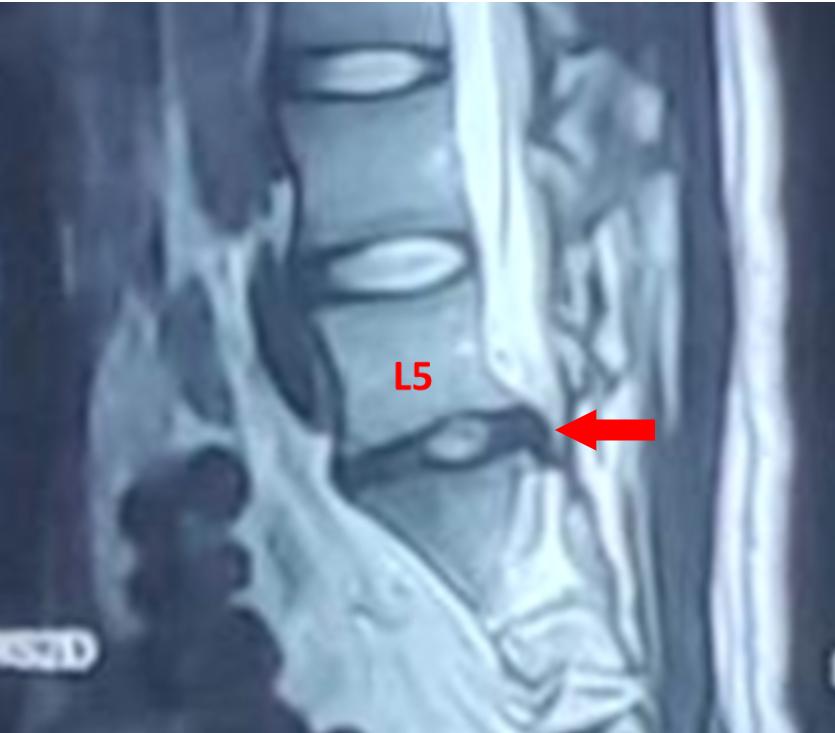

红色箭头:突出的L5/S1椎间盘

在家人的陪同下,小祁到家附近医院就诊,经腰部椎磁共振检测发现,小祁腰5/骶1椎间盘左后突出。

红色箭头:受压的S1神经根